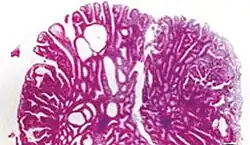

Hyperplastic polyp 0% No dysplasia.[10]

• Mucin-rich type: Serrated ("saw tooth") appearance, containing glands with star-shaped lumina.[11] Crypts that are elongated but straight, narrow and hyperchromatic at the base. All crypts reach to the muscularis mucosae.[11]

• Goblet cell-rich type: Elongated, fat crypts and little to no serration. Filled with goblet cells, extending to surface, which commonly has a tufted appearance.[11]